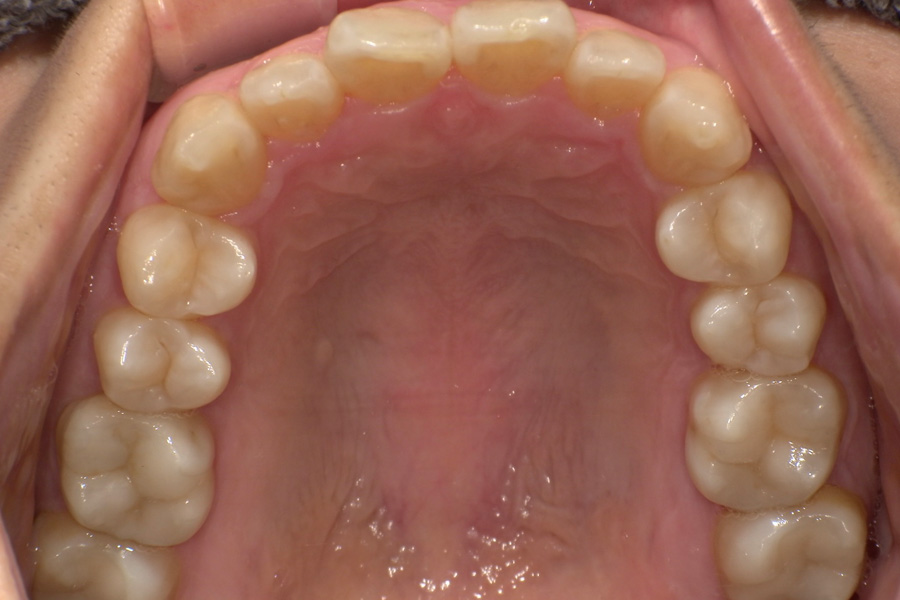

虫歯があるから削ったり悪くなったから抜くのではなく、まずは虫歯と歯周病が起きないようにより良い環境づくりをすること、そうすることによって歯を長く維持することが可能となります。

そのためには、健康状態に関する情報と生活習慣などの状況を把握したうえで、お口の中のリスク評価をおこないます。

その結果をもとに、お一人お一人にあった治療計画をご提案させていただきます。